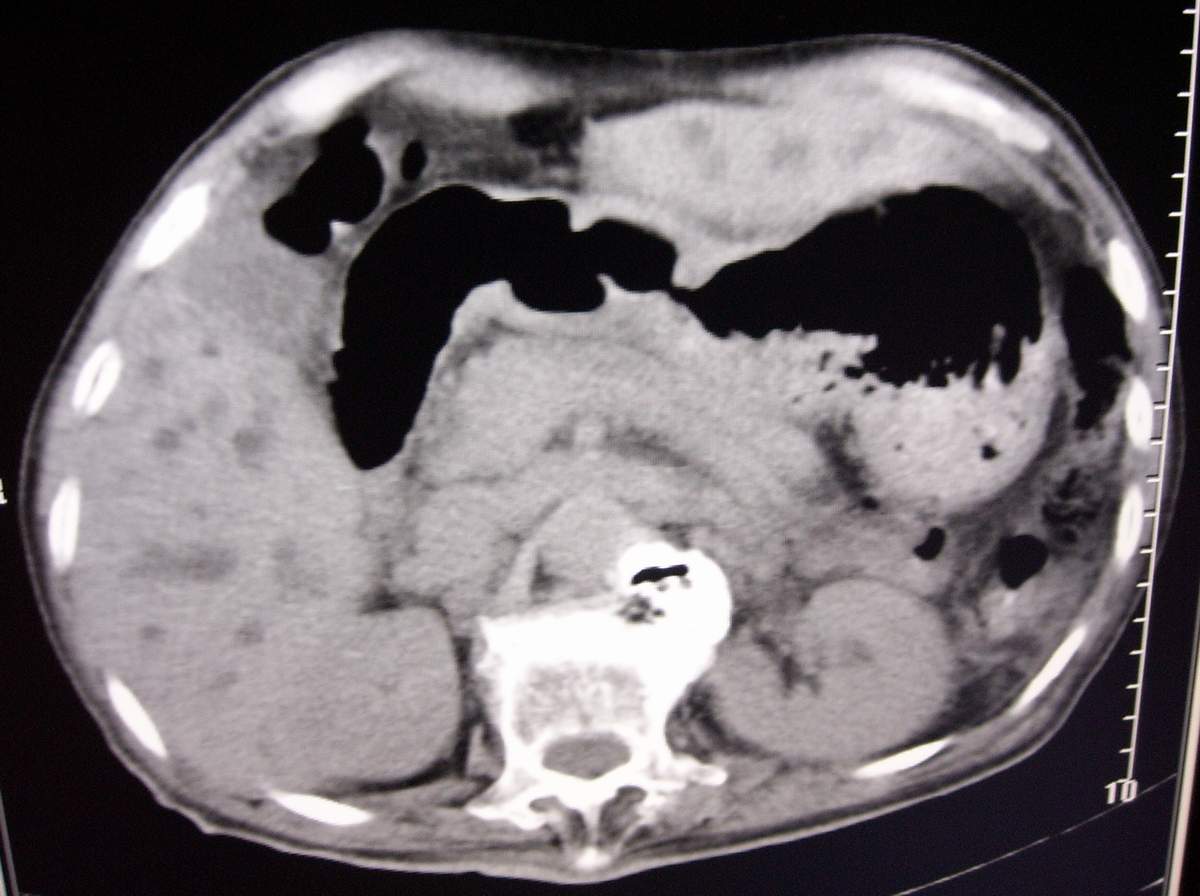

男,77岁,病史不详。

肝内外胆管明显扩张,但是程度较轻,应该是个慢性的过程,增强扫描后未见明显异常强化,胰管增宽、扩张考虑为胰头部占位性病变。

肝内外胆管明显扩张,肝门区见软组织密度肿块,胆囊壁增厚,胆囊扩大。胰头不大。考虑:肝门区胆管细胞癌。

肝内胆管普遍扩张,呈串珠状改变,走行不规则,且右叶胆管周围肝实质密度呈条片状减低,未见占位性病变,外周胆管及胰管扩张不及肝内胆管.胰腺钩突形态正常,胰十二指肠区域未见明显结节及肿块,初步考虑慢性胆管炎可能性大.请结合临床病史.另外用宽窗看一下吉氏筋膜有无增厚.

1 肝内外胆管扩张,肝内明显,胰管扩张,胰头明显增大,符合胰头癌双管征。2 胆囊壁略增厚,胆囊内可见高密度结石影,胆囊炎、胆结石3 左肾囊肿